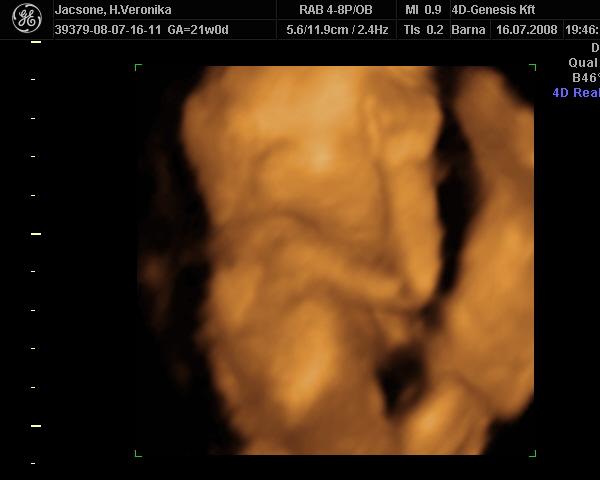

az hogy tényleg lány e már csak a szülésnél fogom megtudni mert a köldök zsinórt a lába közé rakta totáll és azt nem fogja onnan tudni kibűvészkedni már. De nem baj.

képek akkor tovább

Kép

ez mai.